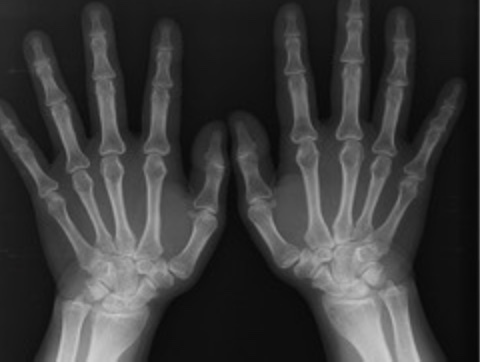

손목터널증후군(Carpal Tunnel Syndrome, CTS)은 손목의 수근관에서 정중신경(median nerve)이 압박을 받아 발생하는 질환입니다. 이 신경은 손바닥과 손가락의 감각 및 운동을 담당하며, 압박이 가해지면 손목과 손가락에 저림, 통증, 감각 이상 등의 증상이 나타납니다. 손목터널은 손목의 뼈와 인대에 의해 형성된 좁은 통로로, 이곳을 지나가는 정중신경과 힘줄이 있습니다.

- 전기생리학적 검사 : 정중신경의 전도 속도를 측정하여 신경의 압박 정도를 확인합니다. 이 검사는 손목터널증후군의 진단에 매우 유용합니다.

- 영상 검사 : 필요에 따라 초음파나 MRI를 통해 손목의 구조를 확인할 수 있습니다.